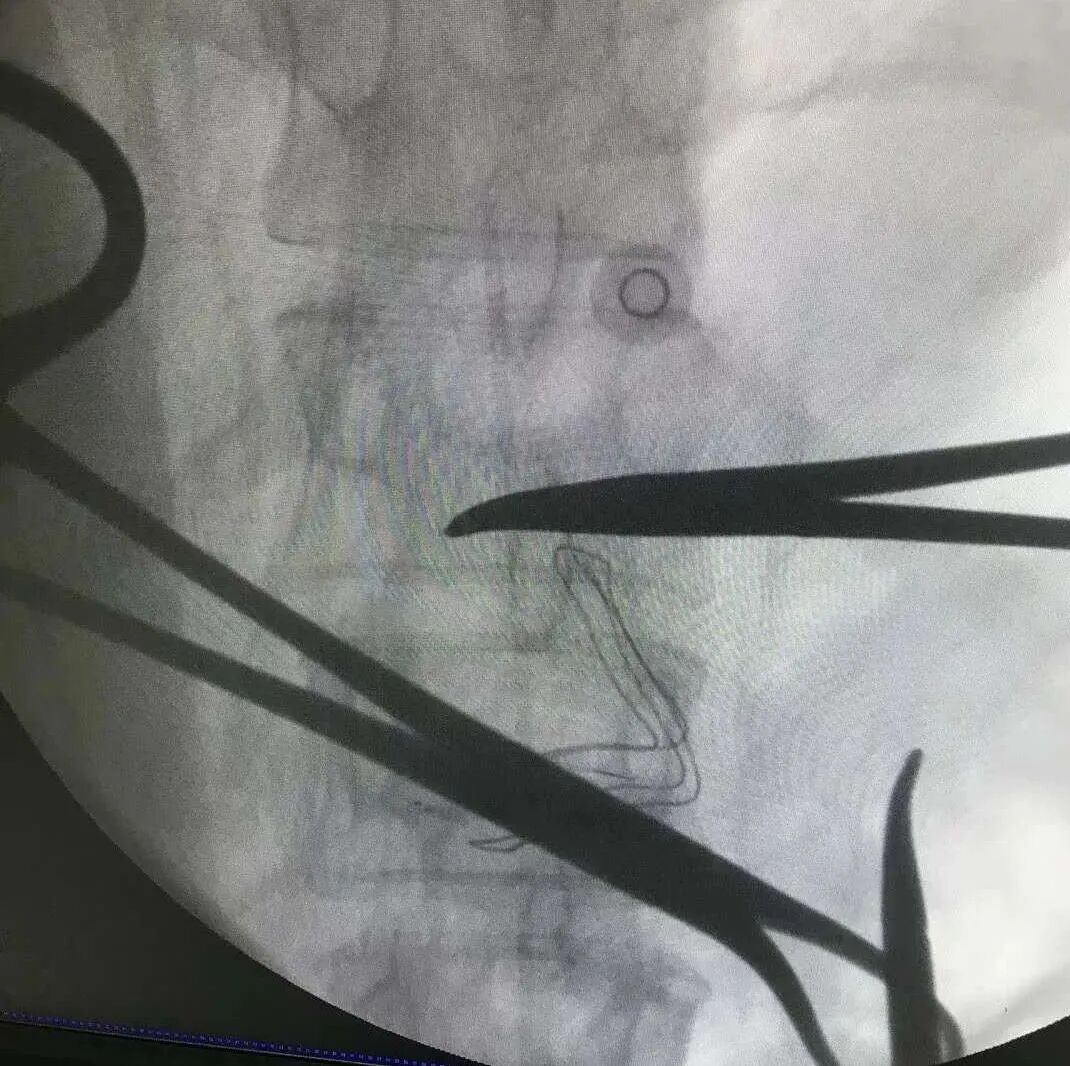

29岁的尹女士一年前被诊断出宫颈癌晚期,经过一段时间的抗肿瘤治疗,病情得到控制。半年前,尹女士觉得腰背部及左侧腹股沟疼痛剧烈,当地医院综合根据病情予以药物及微创治疗,疼痛依然存在。

谢广伦表示,很多晚期癌症患者存在中至重度癌性疼痛,传统的“三阶梯”治疗方案远远不能控制。鞘内镇痛作为一种经济实用的智能化疼痛解决方案,具有创伤小、用药量少、副作用小等优点,而且患者越早应用,治疗效果越好。

肿瘤的治疗有手术、放疗、化疗、免疫治疗等,癌痛的治疗除了传统的三阶梯药物治疗之外,还有很多癌痛治疗方式,如病人自控镇痛、神经阻滞、神经毁损、持续蛛网膜下腔药物输注镇痛等。

这些止痛技术创伤小,治疗效果也很好,对于药物治疗效果不好的疼痛,有效率可达到 90% 左右。